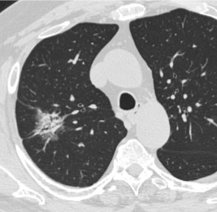

经皮肺结节活检CBCT活检针路径覆盖

7. 在FNAB后立即进行额外的CBCT检查以评估任何并发症(图5)。